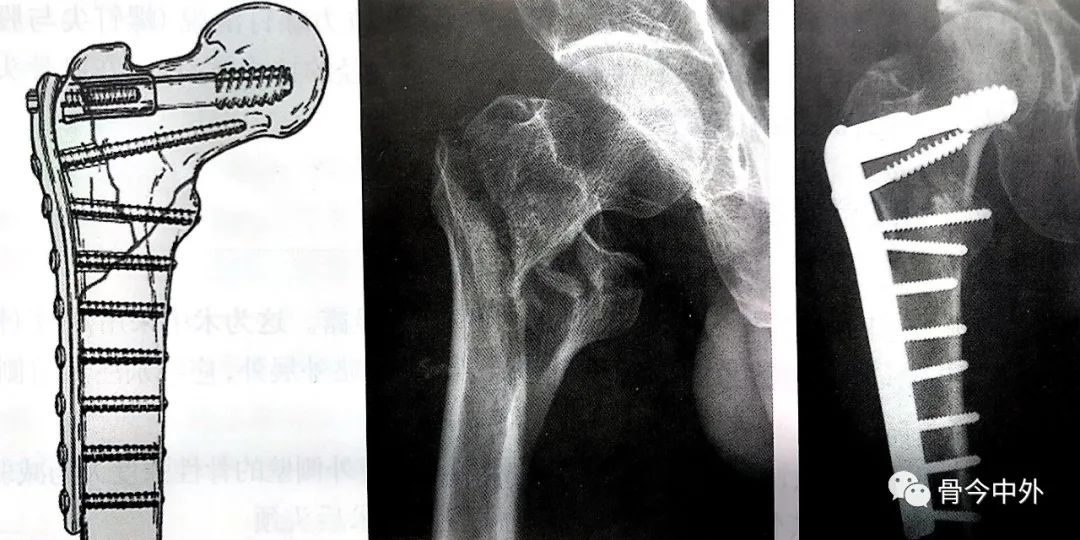

动力髁螺钉( dcs : dynamic condyle screw )

动力髁螺丝钉治疗老年不稳定性股骨粗隆间骨折

动力髁螺钉内固定治疗股骨粗隆部骨折

动力髁螺钉固定时滑动螺钉置入点较高,适用于股骨大粗隆骨质完整或大